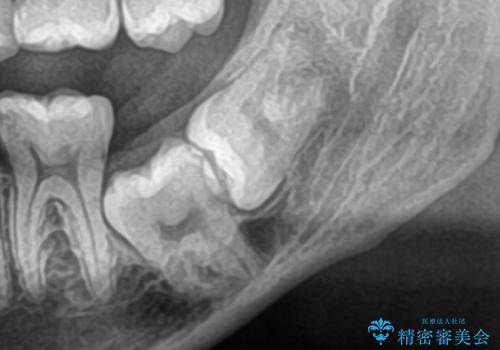

- 「舌が短くて滑舌が悪いので舌小帯を切って欲しい」を主訴に来院された患者様です。

舌小帯切除術を行い舌の可動域を広げ、滑舌の向上を目指しました。

舌小帯切除術は小手術で短い時間で終える事が可能なのでご予約の状況によってはカウンセリング当日に治療を行うことが出来ます。